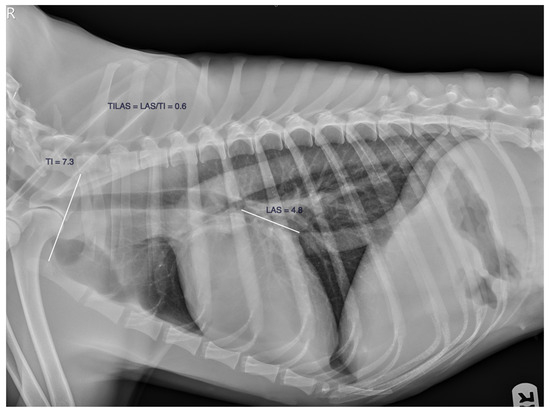

- Szatmári, V.; Hofman, Z.M.M.; van Bijsterveldt, N.J.; Tellegen, A.R.; Vilaplana Grosso, F.R. A novel standardized method for aiding to determine left atrial enlargement on lateral thoracic radiographs in dogs. Animals 2023, 13, 2178. [Google Scholar] [CrossRef]